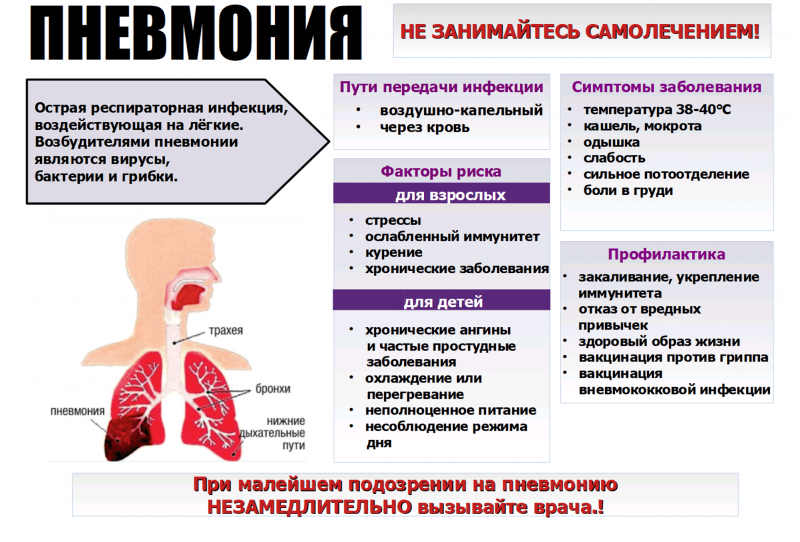

При ОРЗ, ОРВИ, гриппе поражаются альвеолы. Это части легкого, в которых происходит обмен газов между кровью и воздухом. Заболеванию, в зависимости от тяжести, подвергаются одна или две альвеолы и окружающие ткани. В итоге нарушается естественное дыхание, вентиляция, скапливается мокрота.

В этой среде быстро и легко размножаются бактерии, которые провоцируют начало воспалительного процесса в отдельных частях легких. Начинается пневмония.

Если она вызвана COVID-19, то процесс воспаления проходит по-другому. Причиной становятся не бактерии, а вирус. Он нарушает привычную работу альвеол. В них накапливается не только жидкость, но и отмершие клетки. При таком типе воспаления поражаются уже все легкие, а не их части.

Воспаление легких может развиться и без вирусной инфекции. Пневмонию вызывает множество возбудителей.

Это могут быть:

- бактерии (стрептококки, пневмококки);

- грибки (плесневые, дрожжеподобные);

- гельминты.

Воспаление легких может быть смешанной формы, то есть возникать под действием нескольких возбудителей. Во время сезонных заболеваний в несколько раз повышается вероятность заболеть пневмонией.

В группу риска входят:

- курильщики с длительным стажем;

- пациенты после операций, особенно на легких;

- пожилые люди в возрасте после 65 лет;

- ослабленные пациенты после тяжелого лечения;

- люди с хроническими заболеваниями;

- профессиональные строители;

- работники сельского хозяйства.